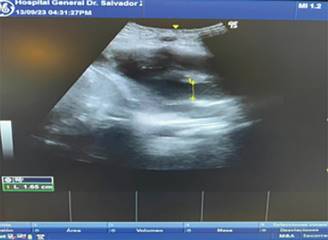

Durante su evolución, se evidencia deterioro hemodinámico con aumento de requerimiento de vasopresores con disminución de SvO2, en la ecocardioscopia se observa hipocinesia del ventrículo izquierdo con una integral velocidad tiempo de 11.1 cm/s, y diámetro de tracto de salida del ventrículo izquierdo de 1.65 cm, con gasto cardiaco de 2.38 L/min (Figura 1 y 2) como deterioro del estado ácido-base con presencia de acidosis metabólica de anión gap elevado (Tabla 3) concomitante con acidosis metabólica de anión gap normal.

Figura 2: Ecocardioscopia. Hipocinesia anterior con dilatación de ventrículo izquierdo con integral velocidad tiempo de 11.1 cm/seg.